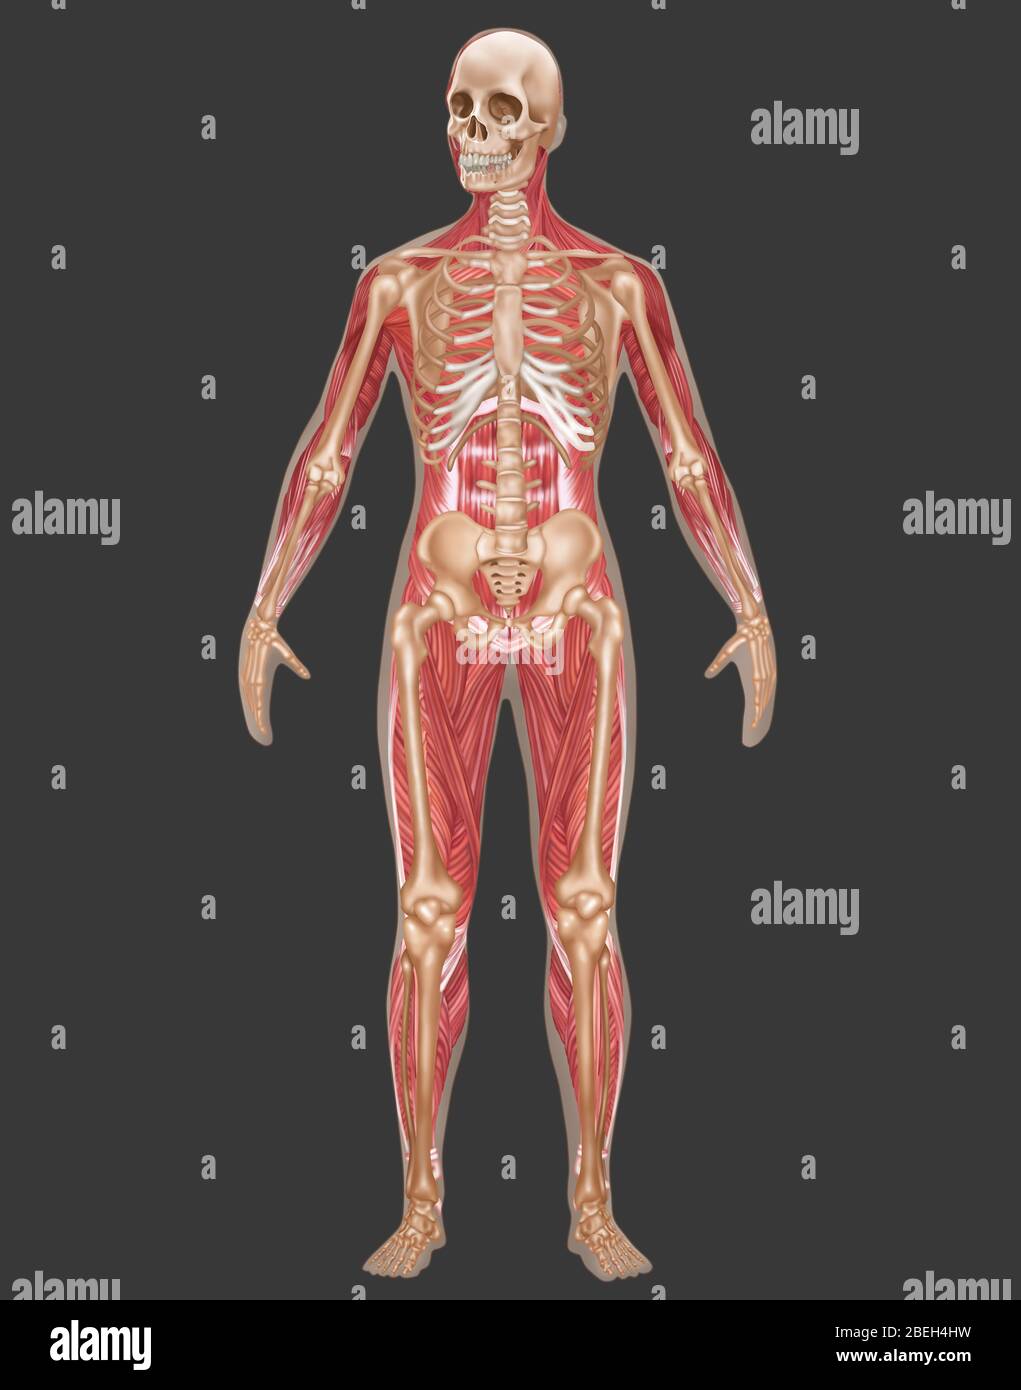

Skeletal & Muscular Systems, Male Anatomy Stock Photohttps://www.alamy.com/image-license-details/?v=1https://www.alamy.com/skeletal-muscular-systems-male-anatomy-image353189325.html

Skeletal & Muscular Systems, Male Anatomy Stock Photohttps://www.alamy.com/image-license-details/?v=1https://www.alamy.com/skeletal-muscular-systems-male-anatomy-image353189325.htmlRF2BEH4GD–Skeletal & Muscular Systems, Male Anatomy